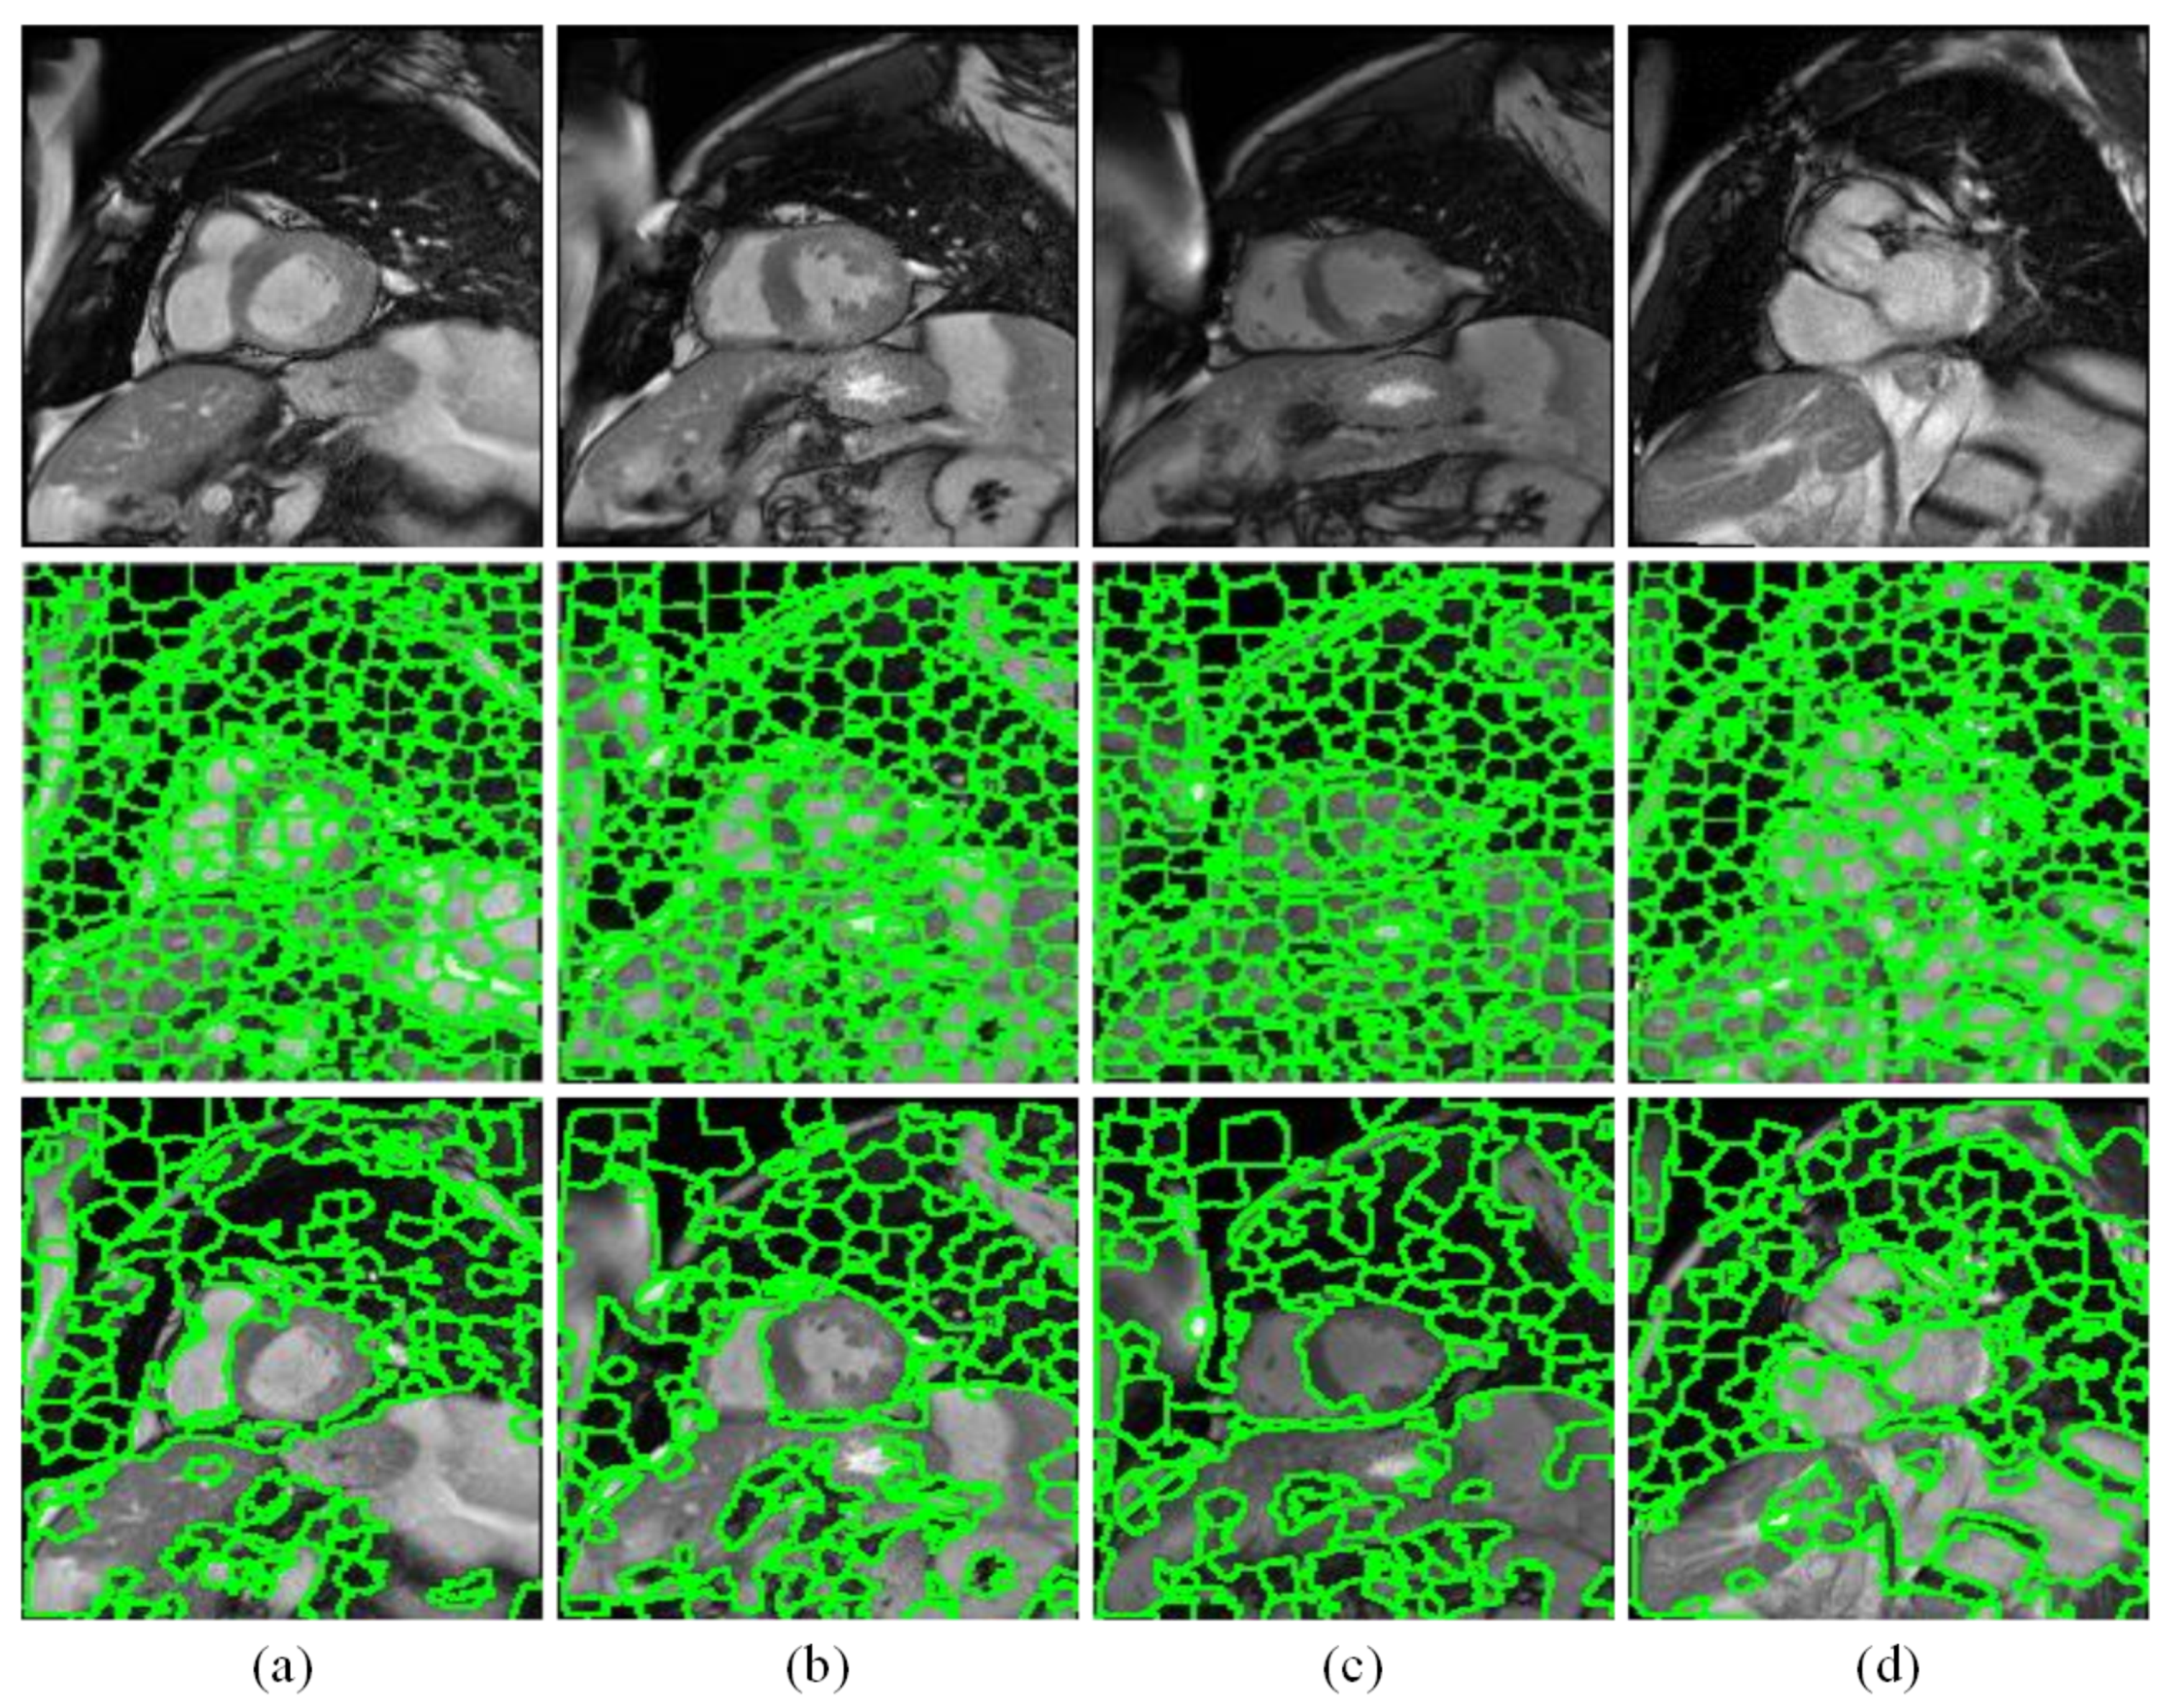

Figure 5 shows some superpixel region fusion examples, from where it can be seen that in comparison to the results of initial SLIC oversegmentation, the left ventricular regions are more remarkable after the processing of proposed discriminative dictionary learning and label fusion. However, the results of regional fusion perform still not very well in some highly complicated images. So it is necessary to compensate them and correct the partially misjudged regions by designing the detection network with the scale adaptive anchors.

Figure 5.

Candidate region generation results. (a–d) are four examples. From top to bottom are the original images, initial superpixel segmentation images, and proposed candidate region images.